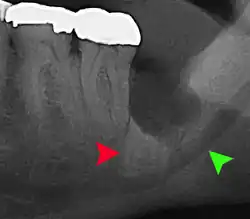

For partially impacted teeth in those over 20 year of age, the most common pathology seen, and the most common reason for wisdom teeth removal, is pericoronitis or infection of the gum tissue over the impacted tooth. The bacteria associated with infections include Peptostreptococcus, Fusobacterium, and Bacteroides bacteria. The next most common pathology seen is cavities or tooth decay. Fifteen percent of people with retained wisdom teeth exposed to the mouth have cavities on the wisdom tooth or adjacent second molar due to a wisdom tooth. The rate of cavities on the back of the second molar has been reported anywhere from 1% to 19% with the wide variation attributed to increased age.[12]

Long-term complications can include periodontal complications such as bone loss on the second molar following wisdom teeth removal. Bone loss as a complication after wisdom teeth removal is uncommon in the young but present in 43% of those of 25 years of age or older.[23] Injury to the inferior alveolar nerve resulting in numbness or partial numbness of the lower lip and chin has reported rates that vary widely from 0.04% to 5%.[23] The largest study is from a survey of 535 oral and maxillofacial surgeons in California, where a rate of 1:2,500 was reported.[26]

Coronectomy

Coronectomy is a procedure where the crown of the impacted wisdom tooth is removed, but the roots are intentionally left in place. It is indicated when there is no disease of the dental pulp or infection around the crown of the tooth, and there is a high risk of inferior alveolar nerve injury.[32]

Coronectomy, while lessening the immediate risk to the inferior alveolar nerve function has its own complication rates and can result in repeated surgeries. Between 2.3% and 38.3% of roots loosen during the procedure and need to be removed and up to 4.9% of cases require reoperation due to persistent pain, root exposure or persistent infection. The roots have also been reported to migrate in 13.2% to 85.9% of cases.[32]